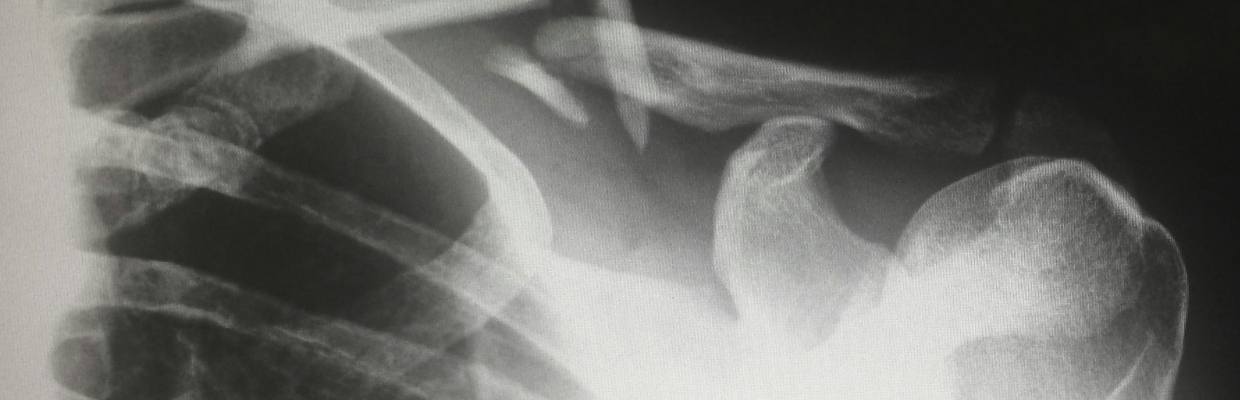

Fracturile de clavicula sunt o problema de sanatate des intalnita, afectand atat adultii cat si copiii. Aceasta leziune se manifesta prin intreruperea integritatii claviculei - osul lung si subtire, asemanator formei literei „S”, care face legatura intre umar si partea superioara a pieptului. Cauzele comune ale fracturii de clavicula sunt traumele la nivelul umarului sau bratului. In cadrul populatiei adulte, fractura de clavicula constituie aproximativ 5% din totalul fracturilor osoase. In randul copiilor, in special cei sub sapte ani, fractura de clavicula este chiar mai frecventa, reprezentand cel mai comun tip de fractura. Un aspect deosebit in aceasta categorie de varsta este fractura claviculei survenita in timpul nasterii, cauzata de diverse traumatisme. Trebuie sa se acorde atentie prompta si adecvata acestei leziuni. Neglijarea unei fracturi de clavicula poate duce la complicatii serioase, cum ar fi ruptura coafei rotatorii - un grup de muschi si tendoane esentiali in mobilitatea si functionalitatea umarului. Un diagnostic si tratament timpuriu sunt esentiale pentru o recuperare optima si prevenirea unor probleme pe termen lung.

Clavicula, un os remarcabil atat prin forma sa unica, cat si prin functia sa esentiala, constituie o veriga vitala intre stern si umar. Aceasta structura osoasa, cu o eleganta geometrica ce aminteste de litera S, este ancorata de stern printr-o articulatie speciala, cunoscuta sub denumirea de articulatia sternoclaviculara. Aceasta conexiune, remarcabila prin adaptabilitatea sa, implica cartilajul ca element de legatura si de amortizare. La extremitatea opusa, clavicula se intalneste cu partea superioara a omoplatului, mai exact cu acromionul, formand astfel articulatia acromioclaviculara. Acesta este un punct de pivot esential pentru mobilitatea si flexibilitatea intregii zone a umarului. Rolul claviculei in biomecanica corpului este crucial. Acest os nu doar ca sustine umarul, dar distribuie si absorbtie socurile si presiunile ce apar in timpul miscarilor sau al accidentarilor. De exemplu, o cadere pe umar sau pe bratul intins nu doar ca solicita umarul, dar transfera o parte considerabila a impactului catre clavicula. Aceasta proprietate face ca osul sa fie predispus la fracturi, fiind unul dintre cele mai frecvent afectate oase in cazul traumatismelor.

Fracturile claviculei sunt un tip comun de leziune, ce pot varia in gravitate si complexitate. Un aspect cheie in clasificarea acestor fracturi este modul in care fragmentele de os se deplaseaza si interactioneaza dupa ruptura. De exemplu, fracturile cominutive sunt caracterizate prin prezenta a mai mult de trei fragmente de os.

Un alt criteriu important in clasificarea fracturilor claviculare este alinierea fragmentelor osoase. In unele cazuri, bucatile de os raman aliniate (fracturi fara deplasare), in timp ce in alte situatii, fragmentele se deplaseaza si necesita o interventie mai complexa (fracturi cu deplasare). In plus, fracturile de clavicula pot fi clasificate ca deschise sau inchise, in functie de daca fragmentele de os strapung pielea sau nu.

Aceasta clasificare detaliata a fracturilor claviculei este vitala pentru a determina cea mai adecvata abordare terapeutica. Fiecare tip de fractura prezinta particularitati specifice care influenteaza atat tratamentul initial, cat si recuperarea pe termen lung a pacientului.